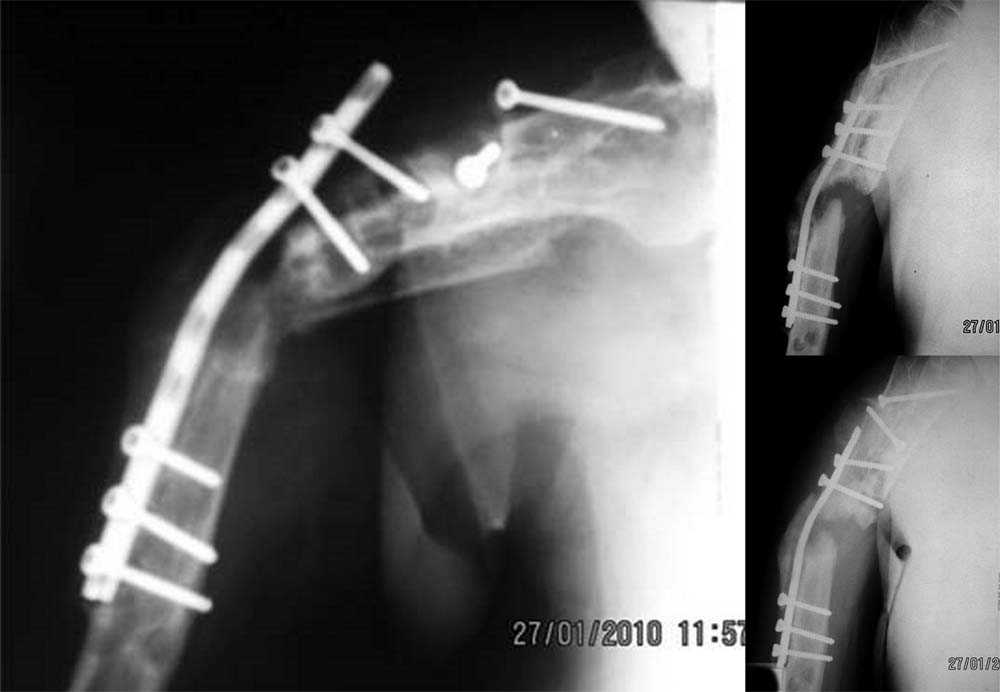

Уважаемые коллеги! Имеется случай ложного сустава плечевой кости с дефектом костной ткани,

последствиями остеосинтеза.

Больной Г., 54 – х лет, получил закрытый перелом правой плечевой кости 2 года назад. Травма

непрямая. Лечился в профильном отделении. Оперирован дважды – первый раз закрытый

блокируемый остеосинтез штифтом Ключевского с просверленными отверстиями для

блокировки. Сращения не достигнуто, остеосинтез несостоятелен, фиксатор удален.

Оперирован повторно – выполнена открытая репозиция, накостный остеосинтез. К сожалению,

какого – либо документального материала о лечении на предыдущем этапе не сохранилось. В

настоящее время ожидается госпитализация в ортопедическое отделение. Локально:

множественные послеоперационные рубцы по всему плечу, состояние их удовлетворительное,

признаков воспаления нет. Визуально варусная деформация плеча. Отведение в плечевом

суставе до 60 град. В с\з – в\з плеча патологическая подвижность, при усилении деформации

пальпаторно определяется верхний конец пластины. Болевой синдром не выражен. В анамнезе

после второй операции – нейропатия лучевого нерва. В настоящее время клиники нет. Хотелось

бы услышать мнение коллег по данному случаю. С уважением. В. Шевченко, г. Хабаровск.